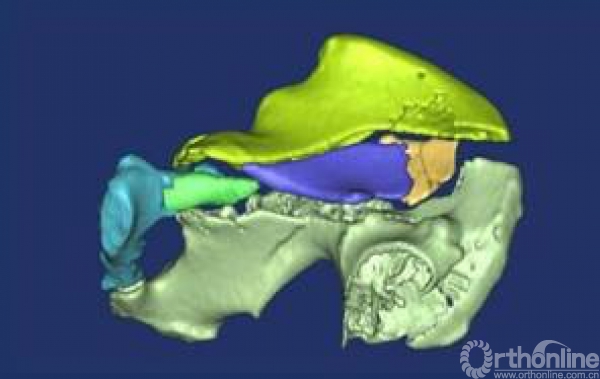

2007年广东省骨科矫形技术与植入材料重点实验室成立,下设数字骨科研究室,对复杂骨科手术进行了计算机辅助观测和个性化术前规划,指导手术;进行了复杂骨盆骨折、小儿骨盆肿瘤、肘关节内翻畸形、先天性半椎畸形脊柱侧弯、髋关节发育不良虚拟手术与快速成形辅助手术; 开展了髋、膝肿瘤个性化设计,CDM定制,肿瘤假体置换、翻修等保肢手术。

引入数字骨科以后,许多以前不可测量的数据都可以通过计算机精确测量,术前计算机辅助可对患者进行个体化手术设计,模拟手术,使复杂骨折能够外科复位,肿瘤能够准确切除,畸形能够理想校正,假体能够精确制作移植。通过这一技术,可以把以前单纯依靠主刀医生经验的复杂性骨科手术精确到1到2毫米,手术成功率明显提高。